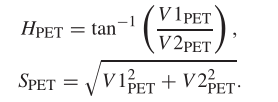

公式

以下公式为RGB与IHS的转换公式

使用IHS(强度,色调和饱和度)来表示PET图像,之类的色调和饱和度都影响颜色信息,因此我们要保持这两个分量的不变,用强度信息来与MRI图像融合。